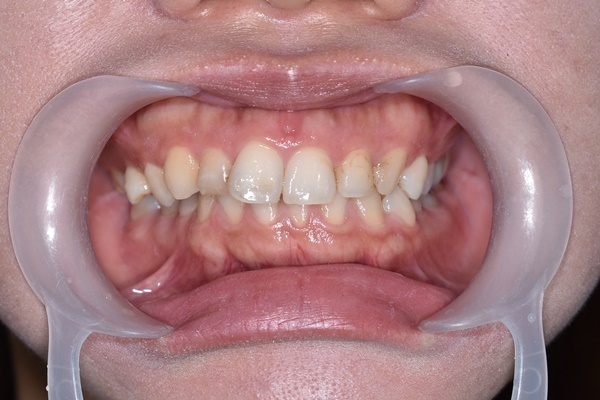

取模方式也跟以往有些不同是採用數位口掃取模,

幾聲嗶嗶聲後螢幕上就能顯現出每個牙齒排列樣貌,

牙齒、牙齦組織好壞通通一覽無遺。

前牙也不會過於凌亂,

經過吳醫師與隱適美討論後,

建議了『隱適美輕矯正』

所謂輕矯正牙套就是針對牙齒凌亂程度不是太嚴重的人,